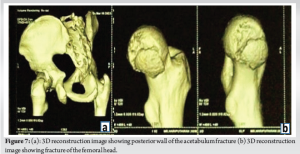

Computed tomography (CT) of the pelvis with hip joints was performed along with CT angiography of the left lower limb which showed intra-articular fracture of the femoral head with avulsion fracture of the posterior wall of the acetabulum (PIPKIN TYPE-IV) (Fig. 5-7). CT-angiography of the lower limb revealed no vascular injuries. Magnetic resonance imaging of the left knee joint was performed showed complete tear of the posterior cruciate ligament (PCL), Grade II tear of the posterior horn of the medial meniscus, and inferior pole of the patella fracture.